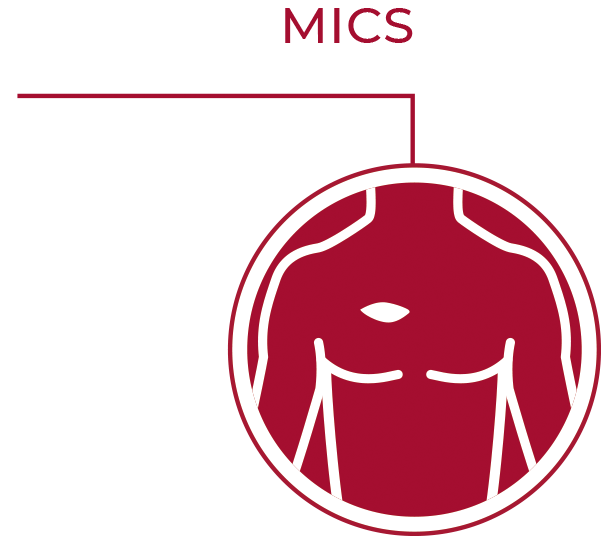

Perceval™ Plus Relyon System

The optimal mix

Perceval Plus is based on the trusted Perceval Platform

The Perceval Platform is based on a sutureless and collapsible design that simplifies the surgical implantation, reducing the impact of surgery and facilitating faster recovery.1,2

Take sutureless AVR to the next level with Perceval Plus RelyON System.

Unique design: unique benefits

Designed for durability

Superlastic stent

- Self-expands in place (no need to knot the sutures), ensuring optimal valve sealing.2

- Reduces the stress transferred to the leaflets.4

- CarbofilmTM coated to reduce inflammatory reaction and favor a gentle endothelialization.5,6,7

Double sheet design

An outer sheet acts as a cushion that minimizes stress transferred to the leaflets.

Fully atraumatic collapsing

The collapsing procedure does not affect the leaflets preventing any possible damage to the tissue.8

Perceval Plus is based on the trusted Perceval Platform, that has shown a linearized rate of SVD of 0.54% per patient-years with a maximum follow-up of 13 years.9

Designed for excellent hemodynamics

Perceval Plus boasts a distinctive design built around a superelastic stent that self-expands in place (no need to knot the sutures), ensuring optimal valve sealing.2

The Nitinol stent allows Perceval Plus to follow the physiological movement of the aortic root during the cardiac cycle, mimicking the native valve.10,11

Designed for the future: the ideal docking station for Valve-in-Valve

Perceval Plus is a valve designed for the future. Not only is it durable,9 but it also gives patients even broader treatment options for their future. Its exclusive stent design allows even circumferential expansion to accommodate future transcatheter valves, making Perceval Plus ViV friendly by design. Thanks to its unique features, all patients eligible for biological AVR may benefit from a Perceval Plus implant.**12,13

Clear visibility

The Nitinol stent provides clear visibility under fluoroscopy and CT scan to identify landmarks which facilitate the ViV procedure.

Even circumferential expansion

The inflow ring can be evenly and circumferentially expanded up to 2.5mm above its nominal size, which allows for hemodynamic advantages and greater compatibility with TAVI models and sizes.

Minimized risk of coronary obstruction

Perceval Plus leaflets remain open when a TAVI is deployed inside it. The sinusoidal struts and the open leaflets create a space between the coronary ostia and the leaflets themselves wich is preserved even after the TAVI deployment.

Minimized risk of sinus sequestration

By design, the Perceval Plus leaflets, when open, do not touch the STJ, thus avoiding sinus sequestration.

Designed for MICS

Perceval Plus RelyON System and Minimally Invasive Cardiac Surgery were made for each other thanks to the sutureless design of the valve and the length and diameter of the new Deliver System. The System allows for minimized incision,11,15 maximized visibility11,12, faster learning curve14,15 and a reduced manipulation of the aortic root.11,15,16

Minimized incision11,12

Thanks to the unique collapsible profile and sutureless design of the valve and the design of the Delivery System, Perceval Plus RelyON System allows a reduced incision size and less surgical trauma.2,11,17

Maximized visibility during implantation11,12

The collapsible profile of the valve and the small diameter of the Delivery System allow the surgeon full visibility of the annulus and of the anatomical structures during implantation and deployment for great confidence and fast, precise positioning at the implantation site.2,8

Designed for fast-track surgery

Fast-track surgery and ERAS have demonstrated many benefits for both the patient18-20 and the hospital.18,20-23 Perceval Plus’s unique design and proven clinical benefits2,17 are expected to enhance the advantages of fast-track and ERAS (Enhanced Recovery After Surgery) protocols even further. Compared to conventional valves, Perceval Plus has shown many advantages, both in full sternotomy and MICS approaches:12,13,17

Designed for ease of use

Take sutureless AVR to the next level with Perceval Plus RelyON System. Perceval Plus is now accompanied by RelyON creating a comprehensive System that allows for a smooth experience for the whole OR team. RelyON has been designed in partnership with surgeons and nurses to ensure an easy and fast Perceval Plus procedure, from unboxing to deployment.

Precise

The RelyON Delivery System delivers Perceval Plus with a single movement of the hand allowing to maintain a firm hold on the device, which in turn facilitates a precise positioning of the valve in the aortic root.

User-friendly

Top-loading valve, self-locking lever, infographics, open-close guide, all-in-one packaging allow for a calm procedure and empower any user to prepare the valve in a quick and effective way.

Optimized for MICS procedures

The design of the Delivery System is optimized for MICS. Both the length and the small diameter of the shaft, together with the collapsible design of Perceval Plus, allow for a minimized incision and facilitated access to and visualization of the implantation site.